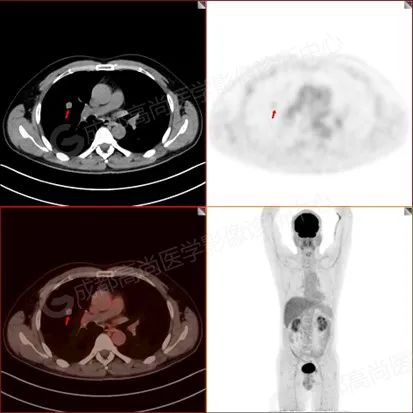

PET/CT 显影图像如下:

【PET/CT 全身 MIP 图】

【PET/CT 融合图】

PET/CT 检查示:

右肺上叶前段及右肺中叶外侧段分叶状软组织结节,该病变骑跨水平裂胸膜,大小约 1.5 cm×1.3 cm×1.6 cm(上下径),边界清晰,其内密度欠均匀,CT 值约 18 Hu,FDG 摄取未见明显增高。

PET/CT 诊断:1. 右肺上叶前段及右肺中叶外侧段见一分叶状软组织结节影(约 1.5 cm×1.3 cm×1.6 cm),该病变骑跨水平裂胸膜,FDG 摄取未见明显增高,考虑为良性肿瘤,请结合病理协诊。